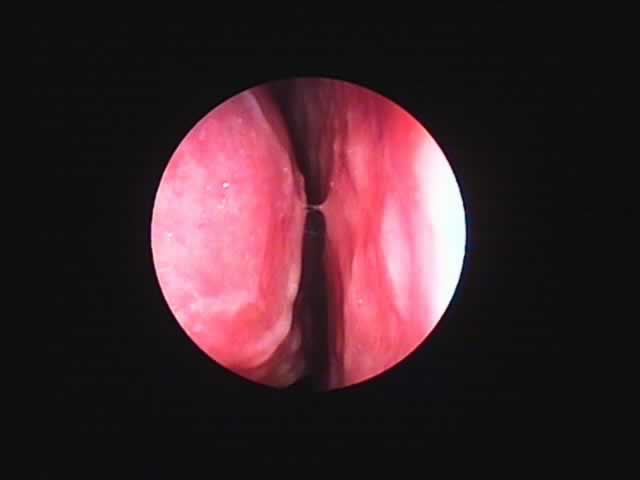

![]() |

右 |

左 |

| 術前 56歳 慢性肥厚性鼻炎 | コブレーション2ヶ月後 |

| いびきも消失。夜間の鼻閉が無くなり本人満足。 |